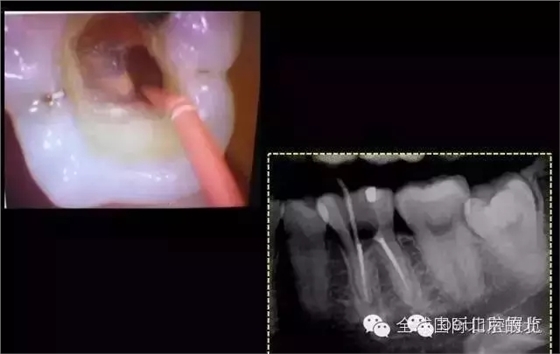

證實確實是遺漏了MB,

是遺漏了,但是又有新的問題出現,無法找到根管口,我一般會用8#Kfile去尋找根管,CBCT上看就在眼前,但是我就是看不到,也無法進入,此時操作也快一個小時了,患者也覺得累了,所以MB暫且停止尋找,因為也確實無法進入,所以把ML,MM根充完成,準確測量長度,AH-Plus,根管糊劑,涂布根管壁,冷牙膠依次充填完成暫封,下周繼續(xù)尋找失落的根管,同時也要把頰側楔缺的位置封閉好,防止再感染,再沒有橡皮障的保護下盡量減少感染機率。

第三次復查:暫封完好,無明顯叩痛。 去除暫封物繼續(xù)尋找MB,繼續(xù)尋找之前,用樹脂將根充完成的DB,DL根管口封閉,MB的位置暫時先不封,防止堵塞MB,剛開始還是找不到MB,然后從頰側的楔狀缺損入手才得以發(fā)現MB的入口,把楔缺擴大去腐干凈。

終于找到MB了,然后把根管口MM,ML封閉,S3機擴,F1.04錐度牙膠試尖,期盼了好久的柳暗花明終于出現。